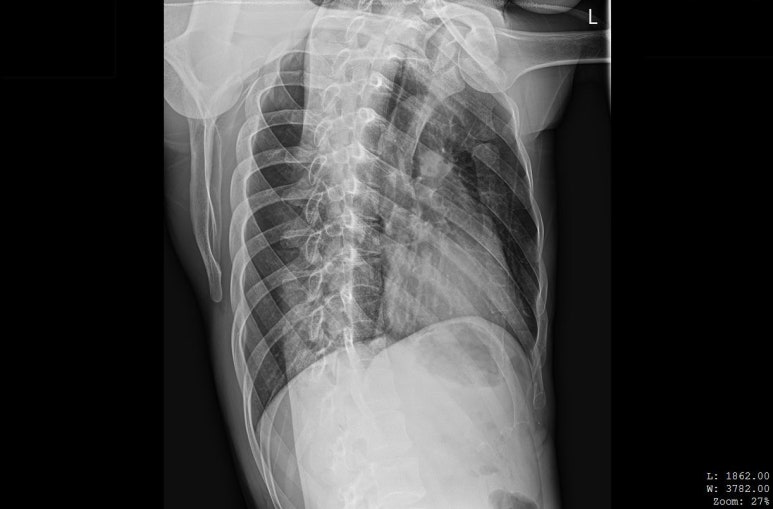

해당 환자분의 X-RAY 영상, 골절선이 보이지 않습니다.

병원에서 X-ray상

뼈는 멀쩡하다고 합니다.